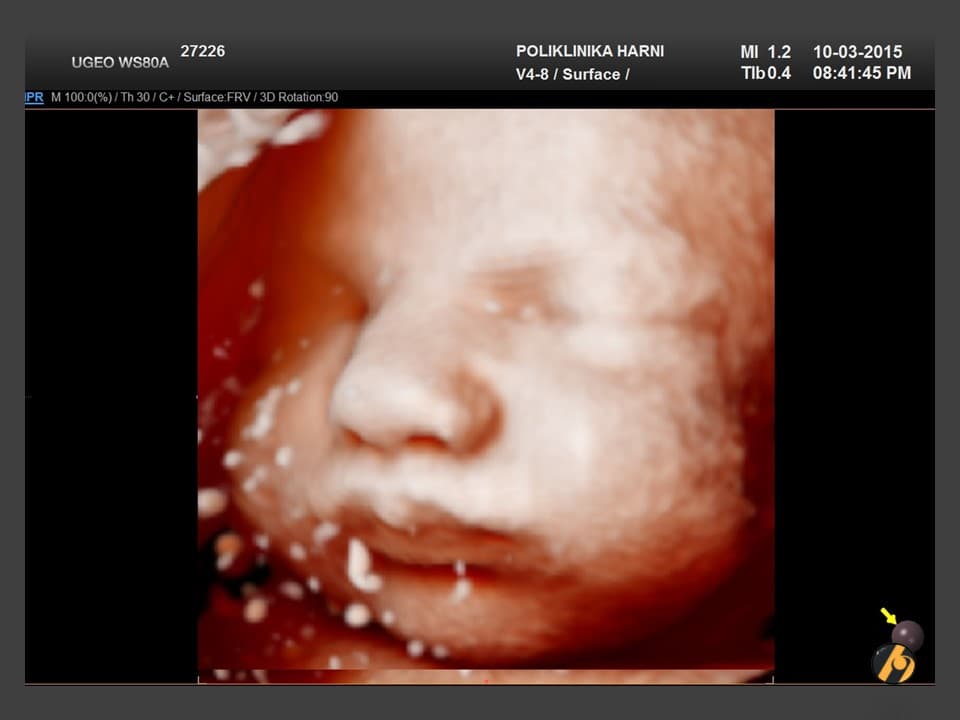

U 39. tjednu trudnoće beba je potpuno razvijena i spremna za život izvan maternice.

Prosječna duljina bebe iznosi oko 50 centimetara, a težina se obično kreće između 3200 i 3600 grama, iako su moguće individualne razlike. Potkožno masno tkivo sada je dobro razvijeno i pomaže bebi u održavanju tjelesne temperature nakon rođenja.

Pluća su u ovoj fazi funkcionalno zrela, dok mozak i živčani sustav nastavljaju sazrijevati i nakon rođenja. Beba ima razvijen refleks sisanja i hvatanja koji će joj omogućiti hranjenje majčinim mlijekom i prve interakcije s roditeljima.

Većina beba sada je u položaju glavom prema dolje, što je najpovoljniji položaj za vaginalni porod. Prostor u maternici postaje vrlo ograničen pa su pokreti drukčiji nego ranije u trudnoći. Oni su sporiji, ali često snažni i jasno osjetljivi.